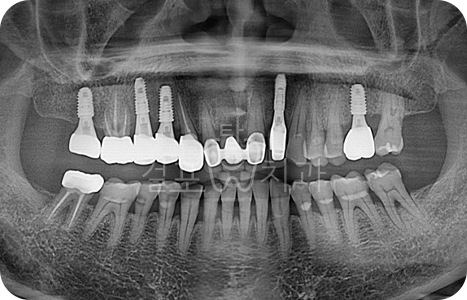

Before

After

• 자연치아를 최대한 보존하면서 꼭 필요한 부분만 임플란트를 식립하였습니다. 광범위한 뼈이식이 필요하였으며 오염되었던 치근 주위로 뼈를 만들어 내야하는 고난도 케이스입니다.

치유가 아직 덜된 발치 부위에 상악동 수술과 3면 뼈이식이 들어가는 고난도 치료였으나 큰 문제 없이 이상적으로 치료되었습니다.